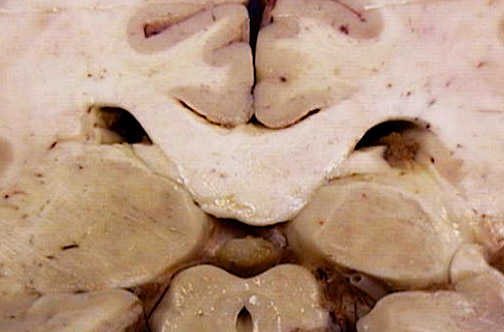

Identify the following regions of the normal brain in the image above: Aqueduct of Sylvius - Pulvinar of Thalamus - Cingulate Gyrus - Choroid Plexus - Pineal Gland - Splenium of Corpus Callosum - Collicular Plate -